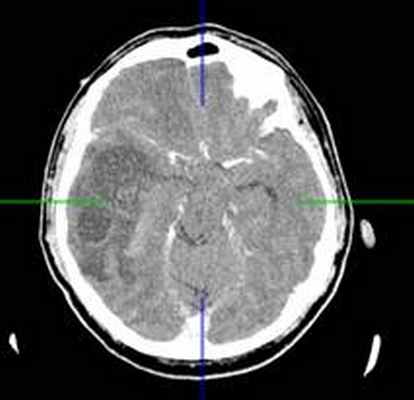

КТ головного мозга с контрастным усилением (24.03.2015): объемное кистозно-солидное образование правой теменно-височно-лобной области. Дислокационный синдром.

(а) МРТ, FLAIR, аксиальный срез: у молодого взрослого с многолетним анамнезом судорог в области коры и субкортикального белого вещества правой теменной доли определяется клинообразное гиперинтенсивное объемное образование. Обратите внимание на отсутствие перифокального отека.

(б) МРТ, постконтрастное Т1-ВИ, аксиальный срез: у того же пациента контрастирования образования не определяется, что является типичным признаком ангиоцентрической глиомы. В смежной с опухолью области часто присутствует участок фокальной кортикальной дисплазии, который должен быть резецирован для предотвращения повторных судорожных приступов. (а) МРТ, Т1-ВИ, аксиальный срез: у шестилетнего ребенка с рефрактерной эпилепсией в структуре коры и субкортикального белого вещества определяется слабовыраженное образование. Обратите внимание на гиперинтенсивные кольцевидные участкичто типично для ангиоцентрической глиомы.